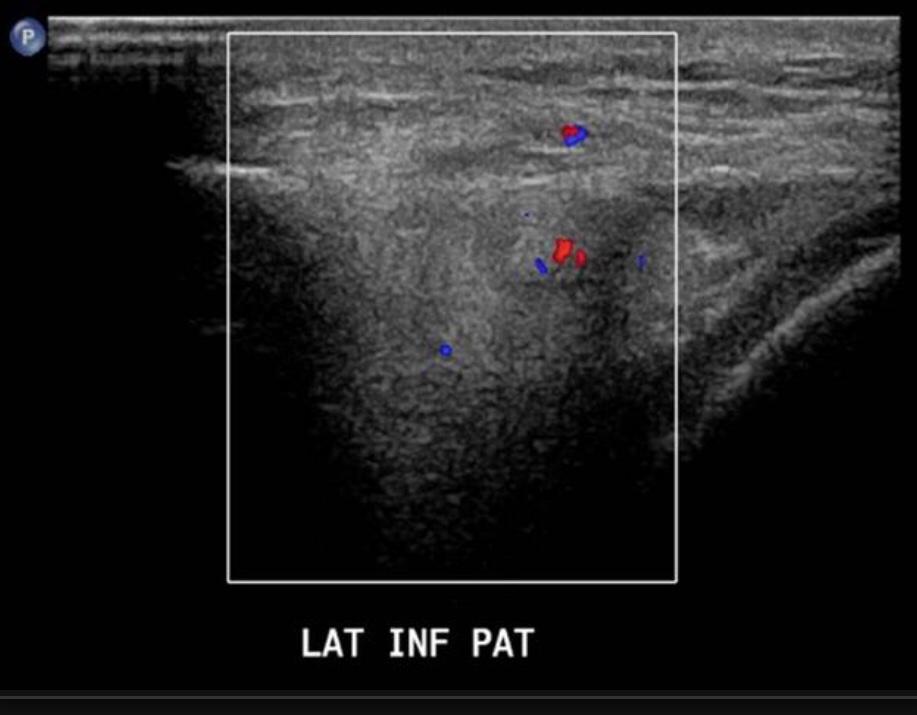

PATELLAR TENDON-LATERAL FEMORAL CONDYLE FRICTION SYNDROME

Patellar tendon-lateral femoral condyle friction syndrome, also known as Hoffa fat pad impingement syndrome, is a common cause of anterior knee pain in active individuals. It is thought to be due to patella maltracking or imbalance of the forces between medial and lateral vastus muscles causing impingement of the superolateral aspect of Hoffa fat pad between the inferior patella and the lateral femoral condyle.

Patients with Hoffa syndrome would present with acute or chronic sharp pain below the patella which is worsened by activities like walking, prolonged standing, wearing high heel shoes or any other activity that puts the knee into full extension. On examination, there may be swelling in the infrapatellar region, with point tenderness at the inferior pole of the patella.

The diagnosis is classically made with MRI and usually occult on radiography and CT. MRI findings include focal area of high T2 signal (edema) at the inferolateral aspect of the patellofemoral joint, within the superolateral portion of the infrapatellar fat pad. A cystic lesion can sometimes be found between the lateral femoral condyle and the lateral retinaculum. Associated findings include lateral patellar subluxation and patella alta (Insall-Salvati ratio greater than 1.2) which are found in around 90% of cases. Conservative treatment is usually successful, although full recovery may take time.